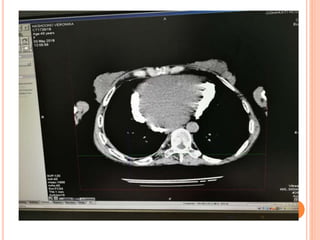

CT scans

Lung Window